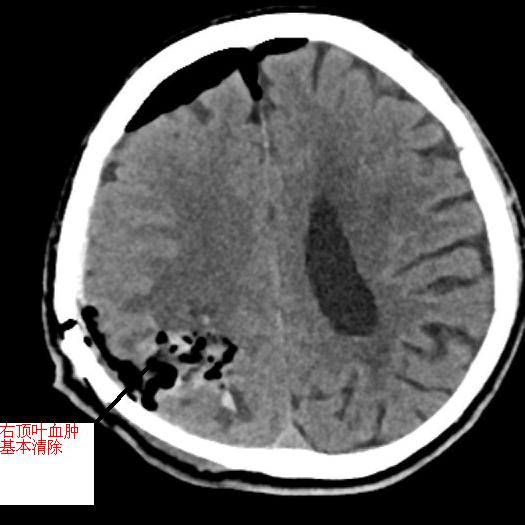

▲左圖為術(shù)前顱內(nèi)血腫,右圖為手術(shù)后原血腫位置,血腫已基本清除

術(shù)后,黃阿伯無(wú)需特殊設(shè)備維持,神志漸清。隨后,經(jīng)康復(fù)治療,神志清楚,對(duì)答配合,左側(cè)肢體肌力較前恢復(fù)。10月初好轉(zhuǎn)后順利出院,囑居家繼續(xù)康復(fù)鍛煉。